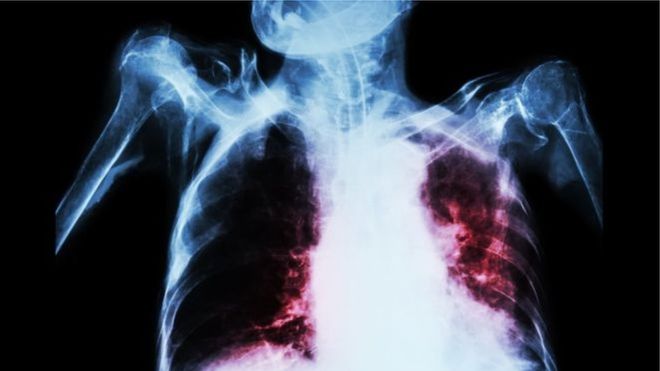

Le nouveau remède qui guérit les souches de tuberculose très résistantes aux médicaments réduit considérablement la durée du traitement.

1,6 million de décès dus à la maladie sont enregistrés par an, dont environ 75 000 en Afrique du Sud, l'un des pays où le nombre de cas de tuberculose est le plus élevé.

L'an dernier, un demi-million de cas de tuberculose résistante aux médicaments ont été recensés dans le monde.